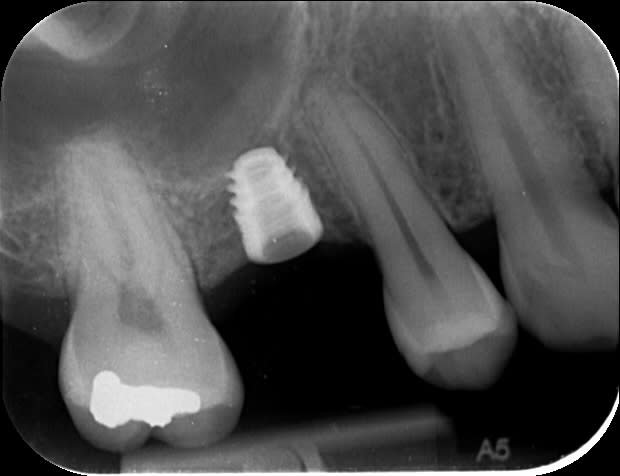

Les implants courts ça marche pas mal, ici un BICON 5x6 sur une 17 d'un confrère

Ici un ID Interactive 6mm : le jour de la pose de l'implant, à 4 mois après pose de la couronne, Bite-wing à 3 ans que je viens de faire à l'instant.

tout chaud.

5x6 mm.

Contrôle régulier du fond du puits, et après le passage du dernier foret, je sens que c'est mou en distal.

le soufflement pas le nez ne produit pas de bulle, petit bout d'éponge hémostatique pour éviter que le filetage n'accroche, et pose.

il y plus qu'attendre...

Merci des avis exprimés.

cette forme trapue avec la connectique à 1mm du nonos je trouve que ça inspire confiance.